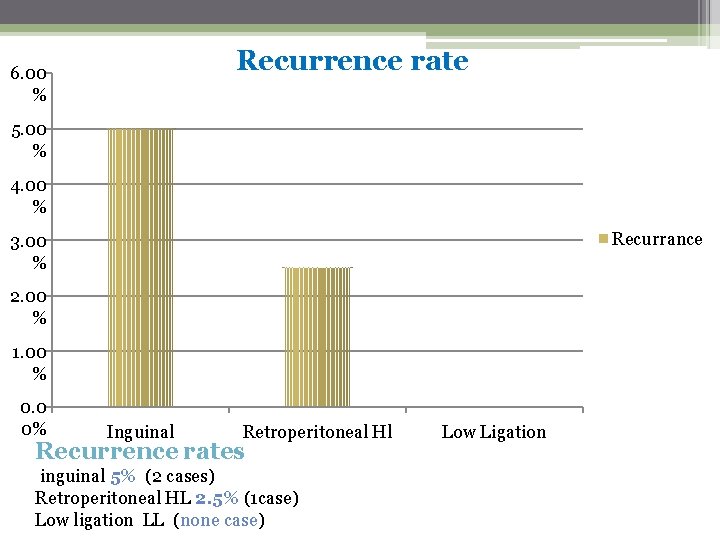

ØWe compare the outcomes of three microsurgical techniques: inguinal high ligation (IHL) =40 patient Retroperitoneal high ligation(RHL) =40 patient Low ligation(LL) =40 Patient we compared the operation time, post operative complication Recurrence rate. The result was…………….

Recurrence rate 6. 00 % 5. 00 % 4. 00 % Recurrance 3. 00 % 2. 00 % 1. 00 % 0. 0 0% Inguinal Retroperitoneal Hl Recurrence rates inguinal 5% (2 cases) Retroperitoneal HL 2. 5% (1 case) Low ligation LL (none case) Low Ligation

Inguinal Retroper itoneal HL 2. 5% 5% Low ligation 0% Recurrence rates